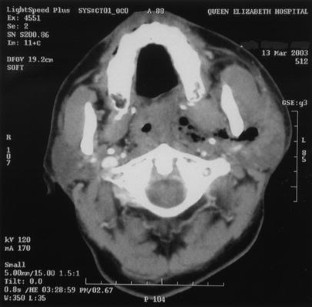

Fig. 4